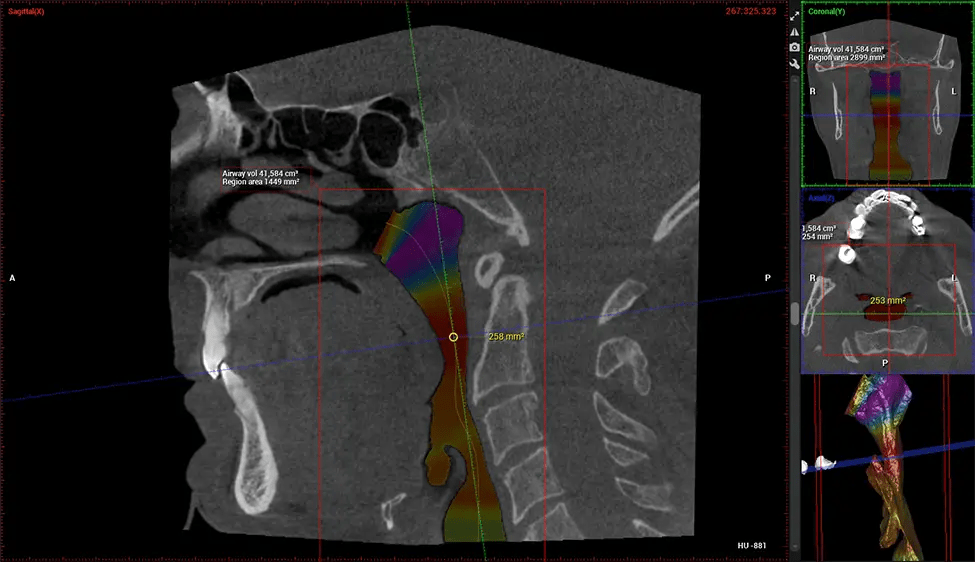

La tomografía computarizada de haz cónico (CBCT) es una técnica de imagen avanzada utilizada en odontología y cirugía maxilofacial para obtener imágenes detalladas en 3D de las estructuras orales y maxilofaciales. En Dr G Dental Studio, nuestros escáneres CBCT utilizan un haz de rayos X en forma de cono y un detector especializado para capturar imágenes desde diferentes ángulos. Luego, una computadora combina estas imágenes para crear una representación 3D de la anatomía oral del paciente.

Esta exploración 3D, llamada tomografía computarizada de haz cónico, le brinda a su dentista una imagen más completa de su anatomía bucal y sus procesos patológicos que una radiografía tradicional. A diferencia de las radiografías convencionales, que capturan una imagen 2D de la boca desde varios ángulos, una exploración 3D toma varias radiografías digitales para una imagen. Proporciona una vista completa de la mandíbula, los dientes, los nervios y los tejidos blandos. Esta vista mejorada permite a los dentistas detectar problemas menores que no son visibles en las exploraciones 2D tradicionales, como muelas del juicio impactadas o fracturas óseas en la cavidad sinusal.

Existen muchos beneficios al utilizar la tecnología CBCT, especialmente en comparación con el formato tradicional de rayos X 2D. Una de las ventajas más importantes de las exploraciones CBCT es que proporcionan mucha más información que las radiografías tradicionales. Una exploración le permite a su dentista ver imágenes desde todos los ángulos de su mandíbula y boca, incluidos los senos nasales, la cavidad nasal, los pómulos y otras áreas circundantes. Esta información adicional ayuda a su dentista a elaborar un plan de tratamiento integral que aborde todos los aspectos de su salud bucal.

Después del proceso de escaneo, las imágenes de rayos X capturadas son procesadas por el software CBCT, que aplica algoritmos para reconstruir una imagen 3D detallada del área escaneada. El software recopila estas imágenes de rayos X individuales y crea una representación digital en 3D de la anatomía del paciente. El dentista o el radiólogo pueden ver y analizar la imagen CBCT 3D reconstruida. Esta imagen se puede manipular, rotar y acercar o alejar para examinar estructuras específicas y evaluar la condición del paciente.